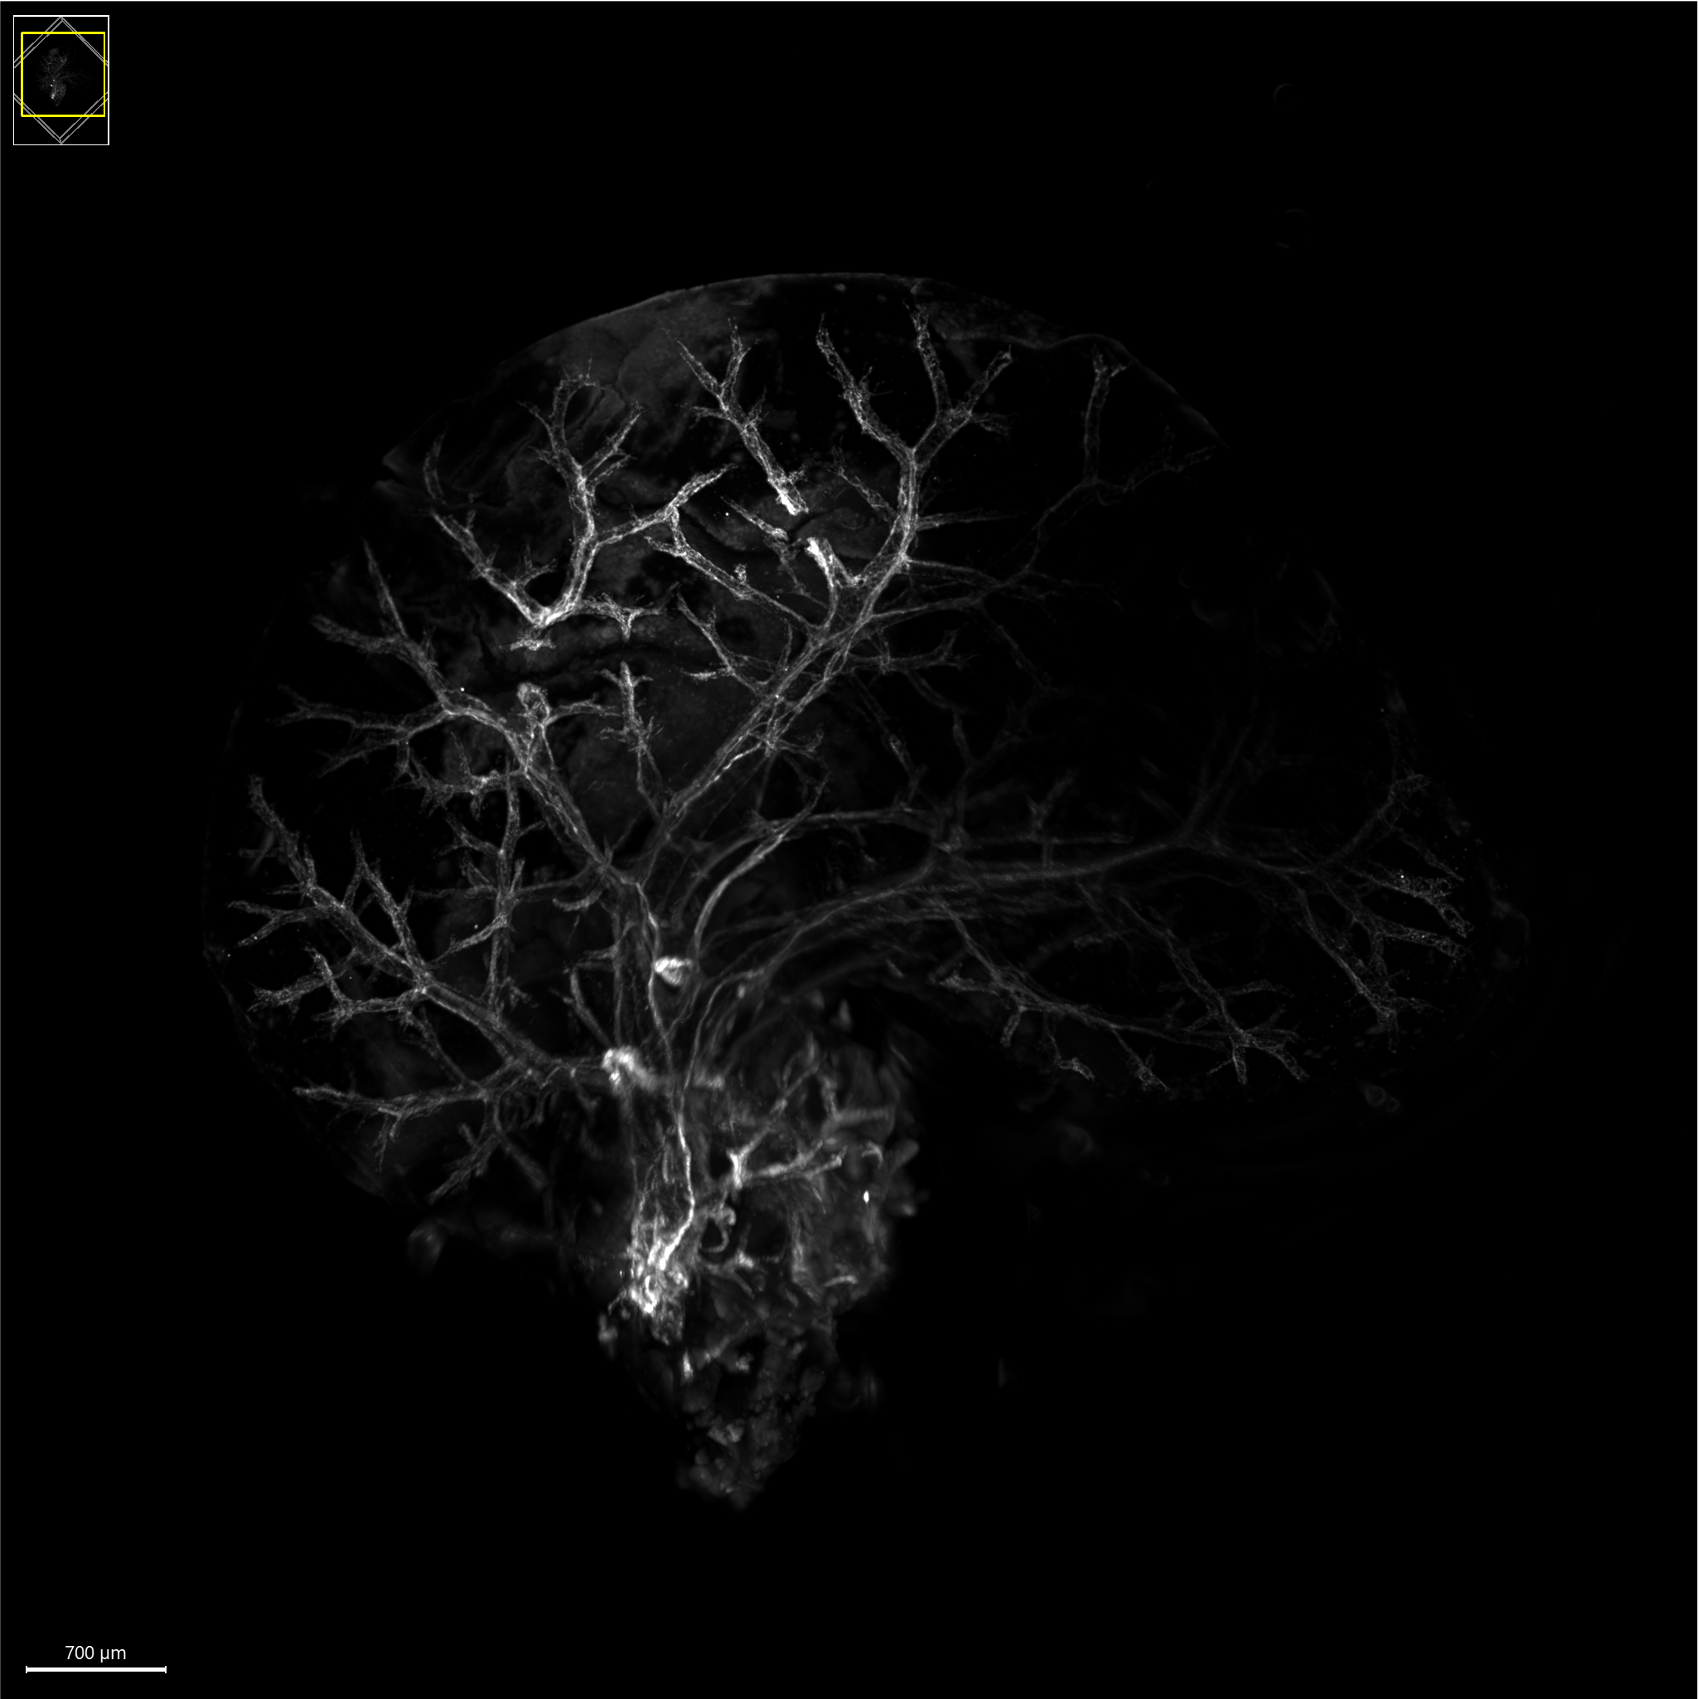

Image Caption: Fluorescence microscopy image showing the highly branched tree of nerve fibres (in white) innervating the mouse liver.

Credit: Andreia Gonçalves and Lena Jansen.